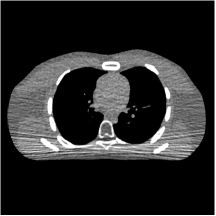

III.C.2. Simulation Framework, Reconstruction Results, and Comparisons

The synthesized low-dose clinical measurements are simulated from regular-dose images at a resolution of mm with a fan-beam CT geometry corresponding to a monoenergetic source at incident photon intensity . The sinograms are of size . The width of each detector column is mm, the source to detector distance is mm, and the source to rotation center distance is mm. We reconstruct images of size with the pixel size being mm mm.

We conducted experiments on one test slice used for parameter tuning (L067-slice 120) and four independent test slices (L109-slice 90, L192-slice90, L333-slice140, L506-slice 100) of the Mayo Clinic data. For PWLS-EP, we ran iterations using relaxed OS-LALM and set regularization parameter . We used the same as the phantom experiments for Algorithm 2. The process of selecting a general set of reconstruction parameters () for the Mayo Clinic test slices is identical to that for the XCAT phantom in Section III.B.2. The selected regularization parameter and the parameters that control the sparsity of the coefficient maps are for ST, , , , , for MARS2, , , , , , , for MARS3, , , , , , , , , , , for MARS5, and , , , , , , , , , , , , , , for MARS7, respectively.

Figs. 8, 9, 10, and 11 show the reconstructions of the four independent slices using the FBP, PWLS-EP, PWLS-ST, PWLS-MARS2, PWLS-MARS3, PWLS-MARS5, and PWLS-MARS7 schemes, respectively. Additional Mayo Clinic experimental results of the parameter tuning case (Fig. 15) are shown in the supplementary document. Table 1 lists the RMSE and SSIM values of reconstructions of the four independent test slices, with the best values bolded. Generally, the five and seven layer models provided the best RMSE and SSIM values. They outperform the single-layer model by HU in RMSE on average. However, the MARS5 and MARS7 models perform similarly. In order to strengthen the benefits of the multi-layer model, Table 2 lists the RMSE of the reconstructions in four different ROIs (shown in the reference of Fig. 11) with seven methods for slice 100 of patient L506. By observing the reconstructed images, we see that although the ST model achieves a cleaner reconstruction result than FBP and PWLS-EP, it still sacrifices some sharpness of the central region and suffers from loss of details. The deeper models have a somewhat more positive effect in terms of maintaining subtle features, which is clearly more essential to clinical diagnosis. Furthermore, as we will discuss later, after considerable parameter tuning, we found that the information contained in residual maps is gradually decreased with the number of layers, eventually vanishing at some layer, which suggests that very deep unsupervised models might not offer significantly better image quality.